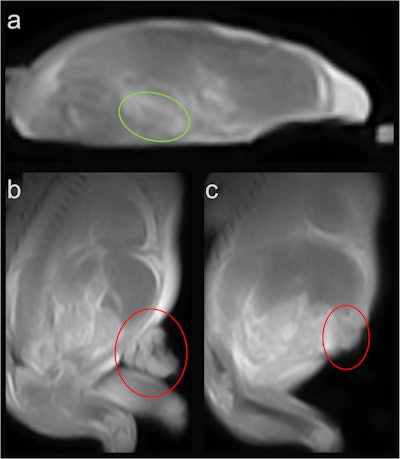

Fetus 3, showing a suspected oligocystic kidney (a, green circle), as well as a defect due to gastroschisis with herniated bowel (b and c, red circle).